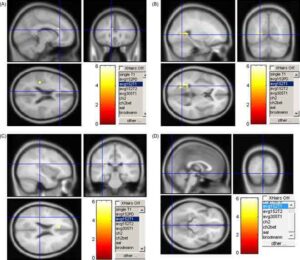

Due diverse tecniche di imaging a risonanza magnetica funzionale hanno permesso di evidenziare che la psilocibina, il principio psicoattivo contenuto...